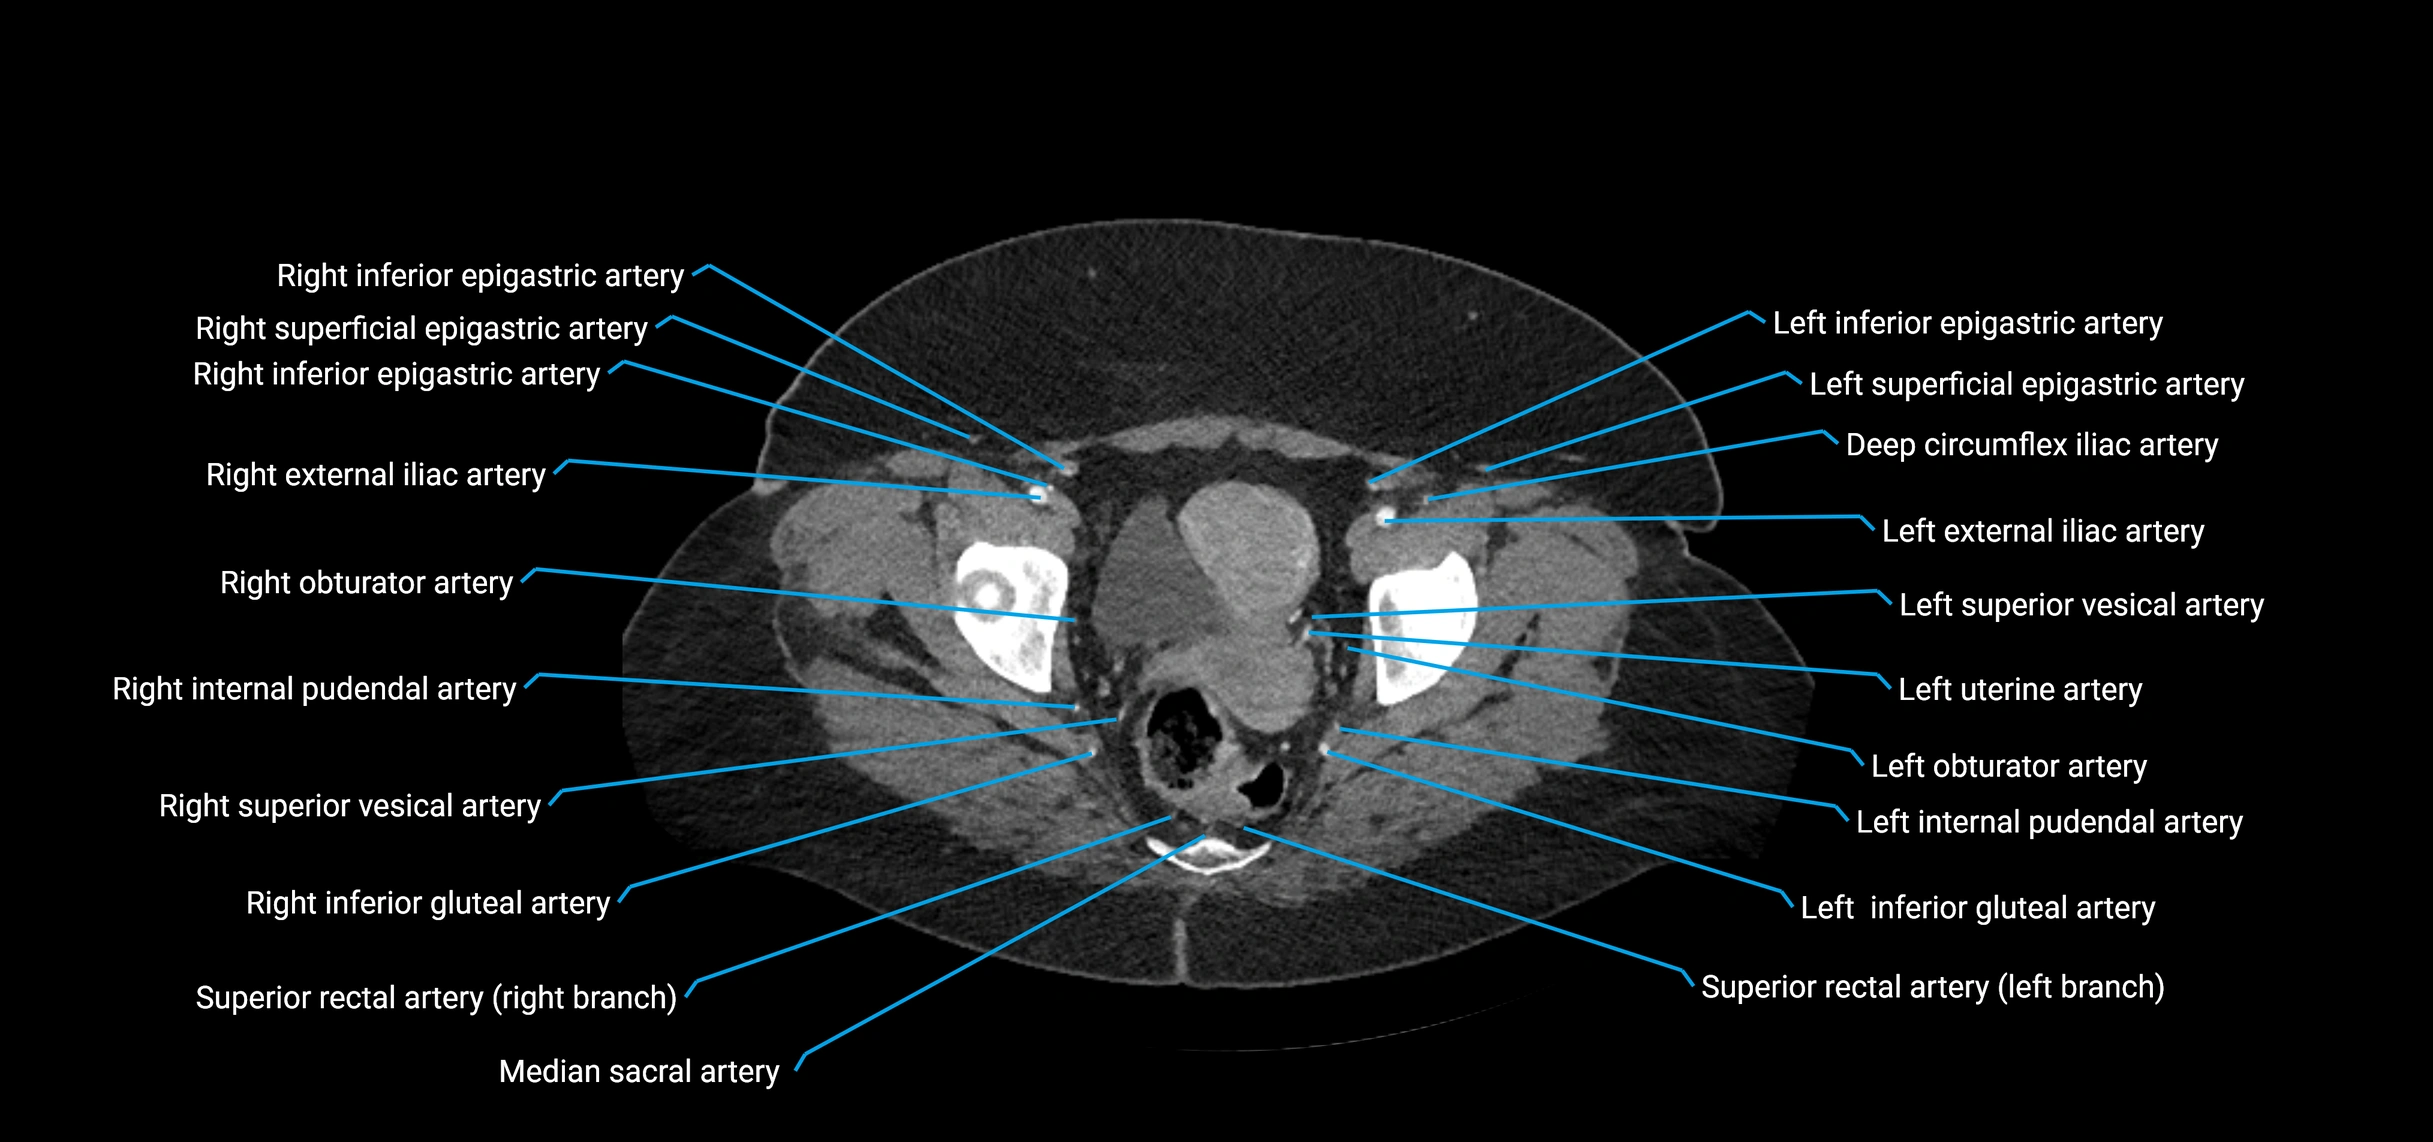

Contrast-enhanced CT (CTA):

• Gold standard for abdominal aortic imaging

• Provides excellent detail of lumen, wall, aneurysm, thrombus, and branch vessels

• Multiplanar and 3D reconstructions help in aneurysm measurement, stent graft planning, and dissection evaluation